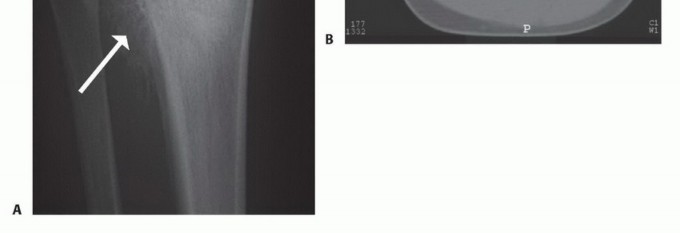

التصوير المقطعي المحوسب والتصوير بالرنين المغناطيسي

يُعد التصوير المقطعي المحوسب (CT) والتصوير بالرنين المغناطيسي (MR) أدوات لا غنى عنها لتحديد مدى تدمير القشرة العظمية، والامتدادات داخل النخاع العظمي، وامتدادات الورم في الأنسجة الرخوة المحيطة. هذه البيانات حيوية لتحديد مستوى استئصال قصبة الساق، والذي يكون عادةً 3 إلى 5 سم بعيداً عن منطقة إصابة الورم داخل النخاع.

يمكن للتصوير بالرنين المغناطيسي أيضاً الكشف عن "الآفات القافزة" (skip lesions)، وهي بؤر ورمية منفصلة عن الورم الرئيسي، والتي قد تؤثر على مدى استئصال قصبة الساق. يوفر الأستاذ الدكتور محمد هطيف تحليلاً دقيقاً لهذه الصور لضمان تحديد هامش جراحي آمن وفعال.

صورة شعاعية توضح ورماً عظمياً في قصبة الساق القريبة.

صورة شعاعية جانبية توضح ساركوما عظمية في قصبة الساق القريبة.

صورة بالرنين المغناطيسي تظهر مدى امتداد الورم داخل النخاع العظمي.